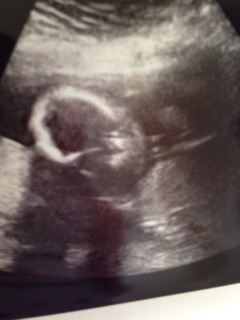

分かりづらいかも知れませんが、左手を頭(おでこ?)に添えながら右手で指しゃぶりをしているところです♪ 口をチュパチュパと動かしており感動。 まだ小さいだけで、すっかり人間ですね(^∀^) 体重は566gとのことで、少し大きめな男の子♪ ずっと逆子のようで、膀胱付近をグイグイされています(´д`;)

写真:22w0d:さきさん:体やらかい